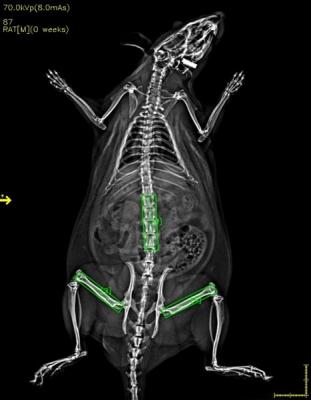

小动物体成分检测